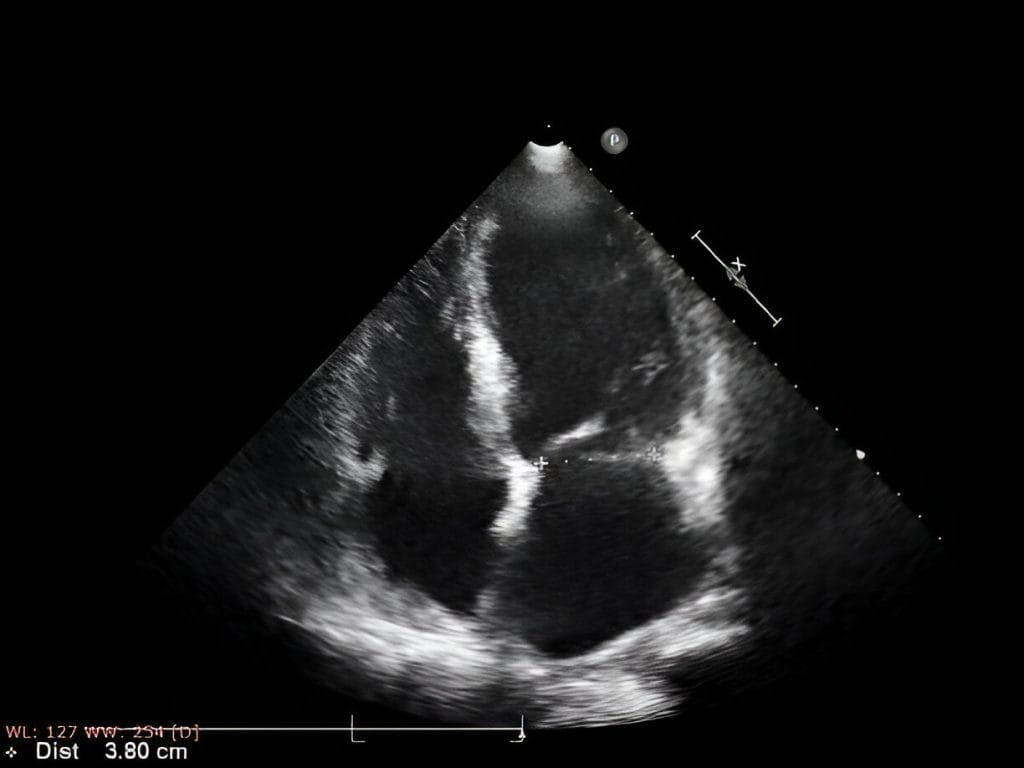

Mild heart attacks are diagnosed by doctors using the following techniques: